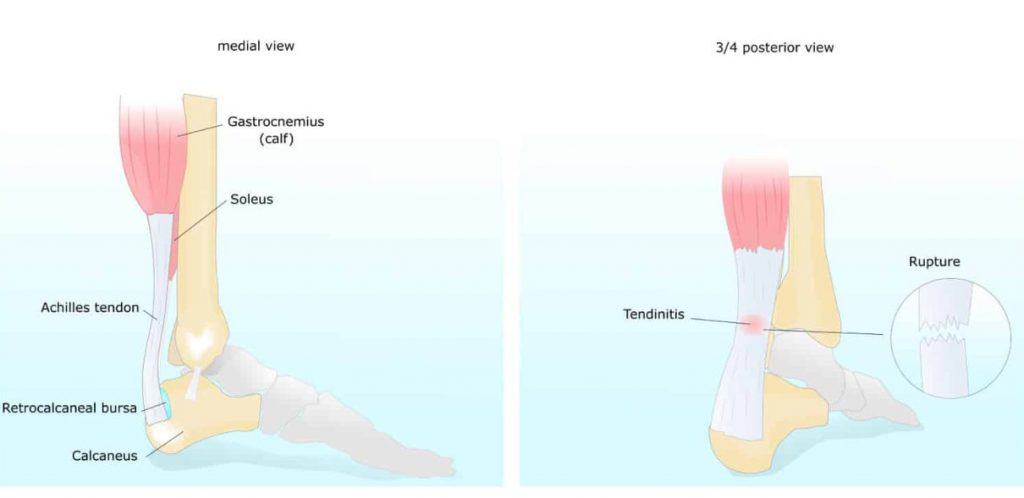

Swollen achilles tendon treatment deals

Swollen achilles tendon treatment deals, How to fix Insertional Achilles Tendonitis deals

Swollen achilles tendon treatment deals

Product Item: Swollen achilles tendon treatment dealsAchilles tendon injuries healthdirect deals, Achilles Tendinitis Symptoms Treatment deals, How to Relieve Achilles Tendonitis in SECONDS deals, Achilles Tendinitis OrthoInfo AAOS deals, Achilles Tendinitis Exercises to Heal and Strengthen Your Tendon deals, Achilles Tendon Pain Causes Treatments Prevention deals, Achilles tendon Overview Mayo Clinic Orthopedics Sports Medicine deals, Achilles Tendonitis Symptoms and Treatment Caruso Foot and Ankle deals, Tendinopathy Symptoms Causes Treatment deals, Achilles Tendinitis OrthoInfo AAOS deals, Chronic Achilles Tendon Pain Diagnosis Treatment HSS deals, Know the Symptoms of Achilles Tendonitis Tendinopathy Gait Happens deals, Achilles tendinopathy Symptoms causes and treatment Bupa UK deals, Achilles Tendon Injuries deals, Swollen Achilles tendon Why does it swell and when can I exercise deals, Heal Your Achilles Tendonitis At Home Achilles Tendon Treatment deals, Achilles Tendonitis FootEducation deals, Achilles Tendinopathy Symptoms Treatments Recovery deals, Achilles Tendinopathy Causes Symptoms Treatment The Feet People Podiatry deals, How to fix Insertional Achilles Tendonitis deals, Achilles tendinitis Symptoms causes Mayo Clinic deals, Back of Achilles Tendon Heel Pain Shoes Orthotics Home Treatment deals, Achilles Tendonitis Causes Symptoms Signs Gleneagles Hospital deals, Achilles Tendinopathy NHS Lanarkshire deals, Achilles Tendinitis in Children Causes and Treatment deals, Achilles Tendonitis Common Symptoms Diagnosis and Treatment deals, Achilles Tendinitis Types Symptoms Causes Diagnosis Treatment and More deals, Achilles Tendinitis River Forest Rheumatoid Arthritis Elmhurst deals, Achilles tendinopathy is when you have micro tears in the tendon deals, Achilles swelling sales pain deals, Achilles Tendon Burning Pain Treatment Achilles Tendonitis deals, Achilles Tendinopathy Causes Symptoms Treatment The Feet People Podiatry deals, Exercises for Achilles pain Three gentle moves to get your rehab going deals, Achilles Tendinosis Treatment Symptoms and More deals, Achilles deals tendon swelling deals.